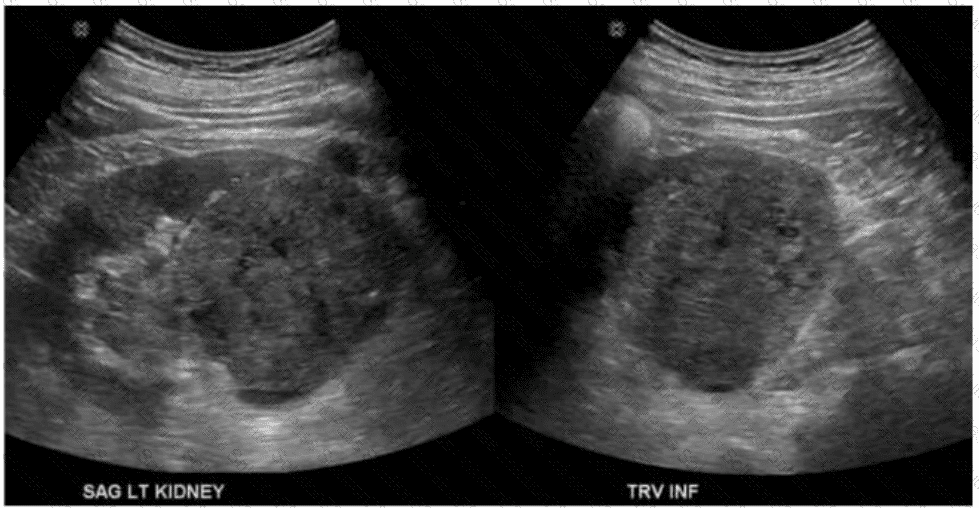

Which condition of the transplant kidney is indicated by the arrows on these images?